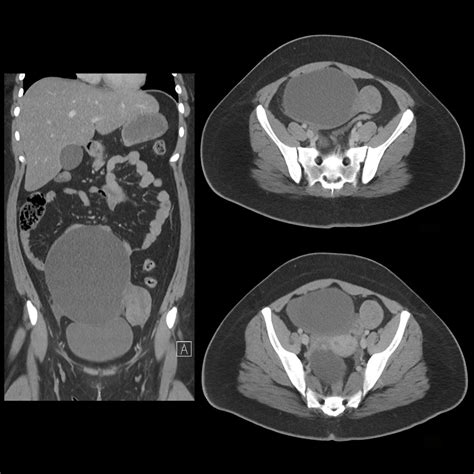

Ovarian Cyst Ct Scan

Discovering you have an ovarian cyst can be an unsettling experience, often leading to a whirlwind of questions about your health and the necessary next steps. While many cysts are harmless and resolve on their own, healthcare providers frequently need to investigate further to rule out complications or more serious conditions. This is where an ovarian cyst CT scan becomes a vital diagnostic tool. By providing detailed, cross-sectional images of your pelvic region, a CT scan helps medical professionals visualize the size, location, and characteristics of a cyst, allowing them to formulate an accurate and effective treatment plan.

A CT scan uses X-ray technology combined with computer processing to create highly detailed images of your organs, soft tissues, and blood vessels. Unlike a standard X-ray, which produces a flat image, the CT scanner rotates around your body, capturing multiple angles that are then reconstructed into a 3D view. This level of precision is crucial for distinguishing between simple fluid-filled cysts and more complex masses that might require surgical intervention.

Once the scan is complete, a radiologist will interpret the images and send a report to your primary doctor or gynecologist. The results will describe the cyst in detail, often noting its size in centimeters, its composition (whether it is fluid-filled, solid, or mixed), and whether there is any evidence of fluid leakage or involvement of adjacent structures.